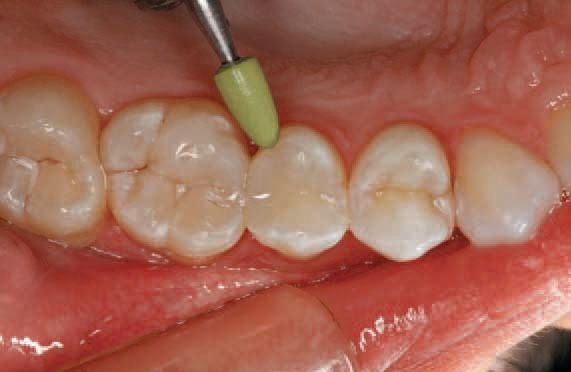

Green polishing points were used to polish the surface (Fig. 12). Pink polishing points were used to achieve a high gloss (Fig. 13). Because the optical properties of this material are designed specifically to match the refractive index of the fillers and polymer matrix, the restoration appeared imperceptible from the surrounding tooth structure because of the enamel-like translucency of 15%.